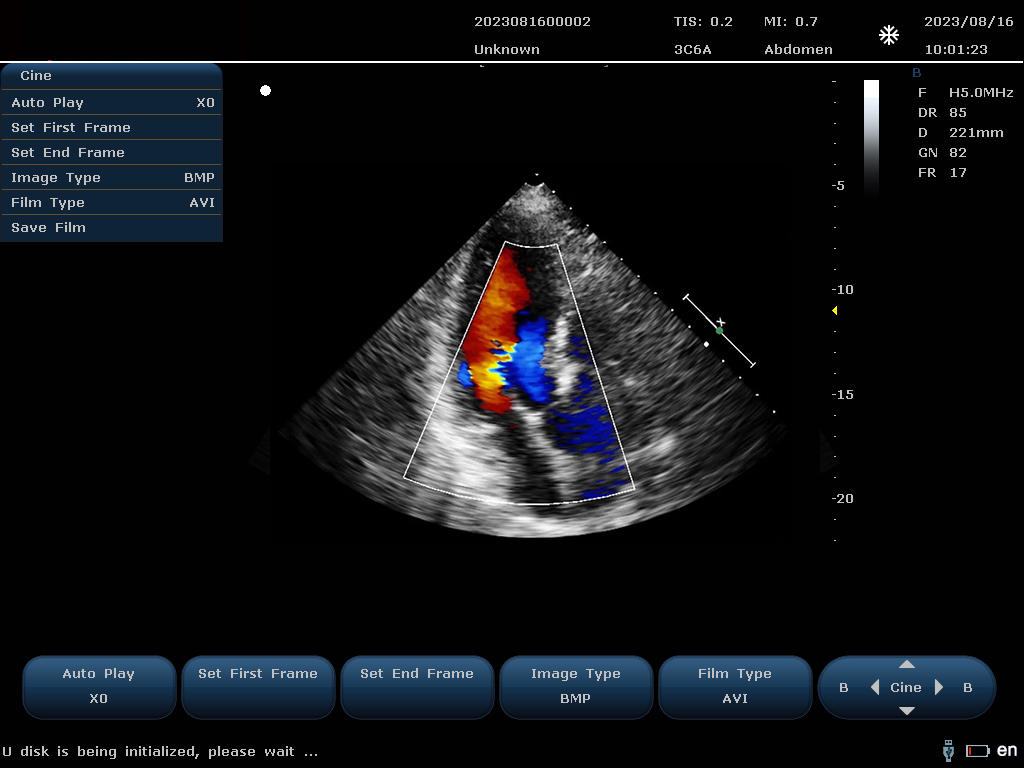

設(shè)備通過檢測這些頻移信號,并利用復(fù)雜的信號處理技術(shù),包括傅立葉變換等,分析血流的方向、速度和分布。彩色編碼后,血流信息被疊加在傳統(tǒng)的黑白超聲二維圖像上,形成彩色多普勒圖像,直觀顯示血流動(dòng)態(tài)。

最終,這些信息轉(zhuǎn)化為圖像顯示在屏幕上,醫(yī)生可以根據(jù)圖像中血流的顏色(通常紅色代表血流朝向探頭,藍(lán)色代表遠(yuǎn)離探頭)和亮度來判斷血流的性質(zhì)和異常情況,如血流速度增快可能指示狹窄,無血流區(qū)域可能意味著阻塞等。